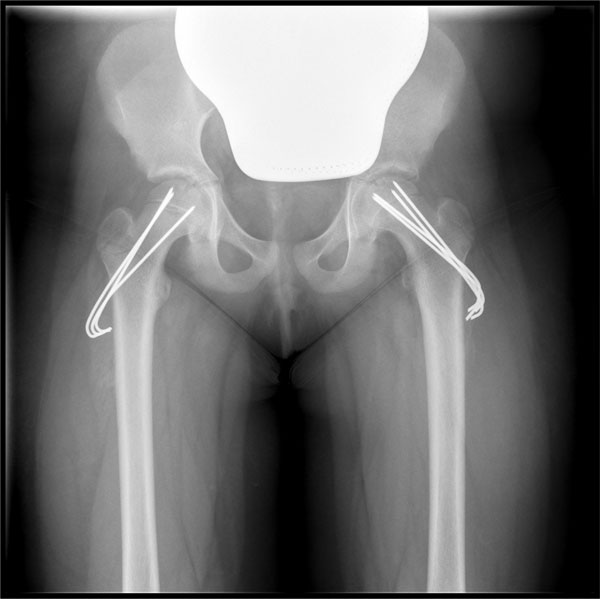

K-Draht Spickung beide

Seiten bei Abrutsch links

Ziel ist es, ein weiteres Abrutschen des Hüftkopfes zu verhindern. Der abgerutschte Hüftkopf wird bei der Operation fixiert, z.B. durch Spickung mit Drähten. Da die Erkrankung in vielen Fällen beidseitig auftritt, werden beide Hüftgelenke operativ versorgt. Bei einem schweren Abrutsch ist es häufig notwendig, weitere operative Maßnahmen am Hüftgelenk durchzuführen.